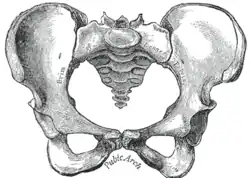

Hueso sacro en el medio, vista frontal. | ||

Imagen de la pelvis femenina, vista anterior.